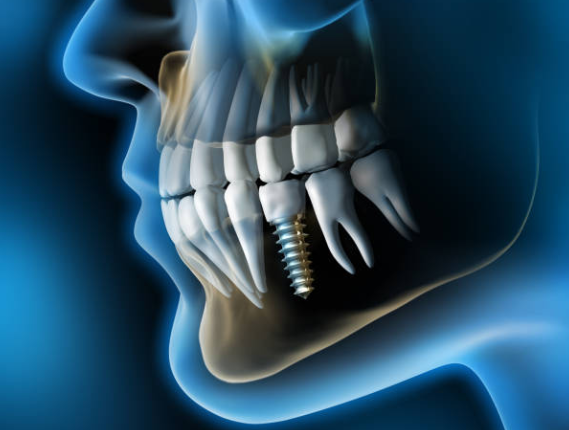

2. 치아 발치 및 1차 시술

임플란트가 필요한 치아의 발치를 실시한 후, 그곳에 1차 시술을 진행합니다. 1차 시술은 턱뼈에 임플란트 인공치근을 식립하고 잇몸을 덮는 과정을 뜻하며, 이 과정에는 필수 기간이 필요하며 일정기간 동안 인공치근과 턱뼈가 잘 붙도록 기다려야 하는데, 일반적으로 아래턱은 약 2~3개월, 윗턱은 약 4~6개월 소요됩니다.